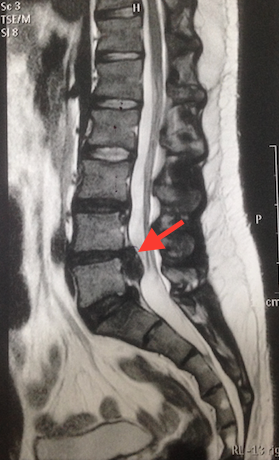

Ou seja, primeiramente, o diagnóstico e o tratamento da hérnia de disco é feito de forma clínica, com análise do paciente, escuta do histórico e fatores de risco. Posteriormente, a confirmação da existência da hérnia e de suas características se dá com a realização de exames de imagem.

O exame padrão ouro para diagnóstico da hérnia de disco é tomografia. Ela deve ser realizada com base na suspeita do médico cirurgião de coluna.

A partir dos resultados e do histórico clínico, o médico poderá solicitar exames de imagem ou eletroneuromiografias para confirmar o diagnóstico de hérnia de disco. A partir daí, ele traça o protocolo de tratamento.